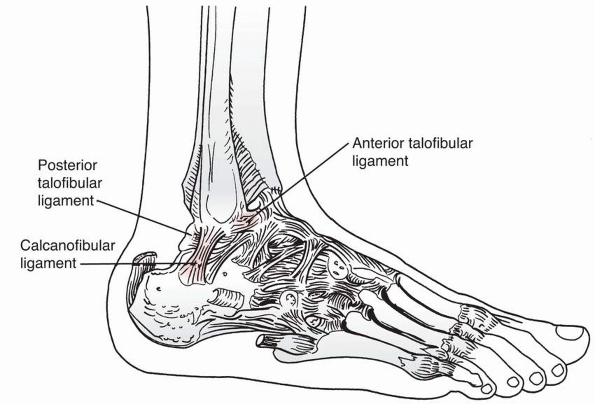

The anterior and posterior inferior tibiofibular ligaments course

inferiorly from the anterior and posterior surfaces of the distal

lateral tibia to the anterior and posterior surfaces of the lateral

malleolus. The anterior ligament is important in the pathomechanics of

“transitional” ankle fractures. Just anterior to the posteroinferior

tibiofibular ligament is the broad, thick inferior transverse ligament,

which extends down from the lateral malleolus along the posterior

border of the articular surface of the tibia, almost to the medial

malleolus. This ligament serves as a part of the articular surface for

the talus. Between the anterior and posterior inferior tibiofibular

ligaments, the tibia and fibula are bound by the interosseous ligament,

which is continuous with the interosseous membrane above. This ligament

may be important in the pathomechanics of what we have termed incisural

fractures.

This ligament arises from the medial malleolus and divides into

superficial and deep layers. Three parts of the superficial layer are

identified by their attachments: tibionavicular, calcaneotibial, and

posterior talotibial ligaments. The deep layer is known as the anterior

talotibial ligament, again reflecting its insertion and origin. On the

lateral side, the anterior and posterior talofibular ligament, with the

calcaneofibular ligaments, make up the lateral collateral ligament (see

Fig. 26-28).

FIGURE 26-28 Lateral view of the ankle demonstrating the anterior and posterior talofibular ligaments and the calcaneofibular ligament.